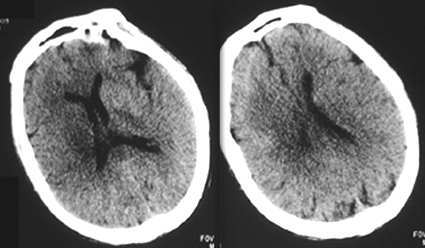

强化。

强化未见壁结节,脑瘤基本可以排除。

ct增强未见低密度灶强化,应该是右侧基底节区脑梗塞并脑水肿。

支持脑梗塞,平扫与增强病变密度好像有改变。